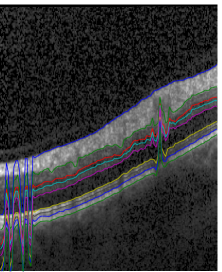

5.2 Generative vs. Discriminative, Transition vs. Boundary Appearance Terms

Following (11), we described the introduction of discriminative appearance models as an alternative to generative ones. Furthermore, we introduced switches βlsuperscript𝛽𝑙\beta^{l} and βtsuperscript𝛽𝑡\beta^{t} in (4) to enable or disable layer and boundary appearance terms, respectively. This section explains why we settled for discriminative boundary terms.

Using the set of healthy circular scans, we tested the model with generative layer as well as boundary terms, i.e. βt=βl=1superscript𝛽𝑡superscript𝛽𝑙1\beta^{t}=\beta^{l}=1. This configuration turned out to be sensitive to distortions of the texture caused for example by blood vessels. The result were initializations above the actual retina, since the model misinterpreted the shaded area as parts of the choroid, as shown in Fig. 8 (a). We then disabled the layer appearance terms, i.e. set βl=0superscript𝛽𝑙0\beta^{l}=0. This solved the previous issue, but spuriously led to some columns being initialized below the retina, due to very high probabilities for some boundary classes caused by relatively small class model variances, i.e. narrow and steep normal distributions. For patches close to the mean, the probabilities for those classes happened to be up to 100100100 times larger than for other classes. This caused false positive class responses in the choroid to displace the whole initialization for these columns, as displayed in Fig. 8 (b).

Switching to discriminative probabilities solved this issue as well, since the local normalization limits all probabilities to 111 and gives each appearance class the same influence. Thus false-positives did not possess the probability mass any more to displace the whole column segmentation, see Fig. 8 (c). Notice that the layer terms, although switched off by setting βl=0superscript𝛽𝑙0\beta^{l}=0, are utilized indirectly, since they contribute to the normalization of terms p(xi,j(c)|yi,j)𝑝conditionalsubscript𝑥𝑖𝑗𝑐subscript𝑦𝑖𝑗p(x_{i,j}(c)|y_{i,j}), see (5). Thus strong layer appearance terms can rule out certain parts of the OCT scan for segmentation.

Refer to caption

(a) βl,βt=1superscript𝛽𝑙superscript𝛽𝑡1\beta^{l},\beta^{t}=1, Gen.

(b) βl=0superscript𝛽𝑙0\beta^{l}=0, Gen.

(c) βl=0superscript𝛽𝑙0\beta^{l}=0, Disc.

Figure 8: (a)-(c) Close-up view of initialization results for different configurations of appearance terms. Switches βlsuperscript𝛽𝑙\beta^{l} and βtsuperscript𝛽𝑡\beta^{t} include or exclude layer and transition appearance terms.